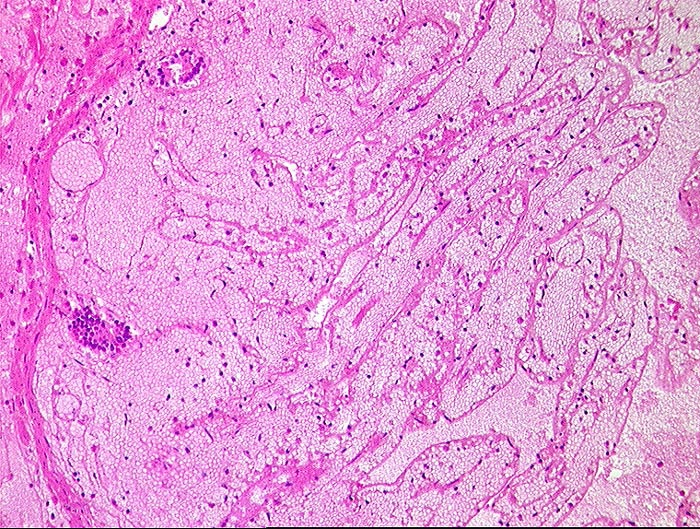

AP/ Mesenterialinfarkt

Mesenterialinfarkt

vaskulär / Durchblutungsstörung

Darm, Anus

Dünndarm

Makroskopie

Pathologischer Befund